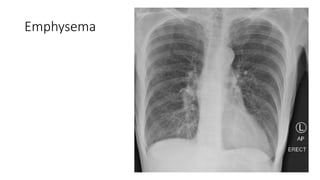

Emphysema

Pulmonary Oligemia Hilar, lobar,and segmental pulmonary arteries appear small Concave or absent main pulmonary artery segment Lung fields have an overexposed or emphysema like appearance